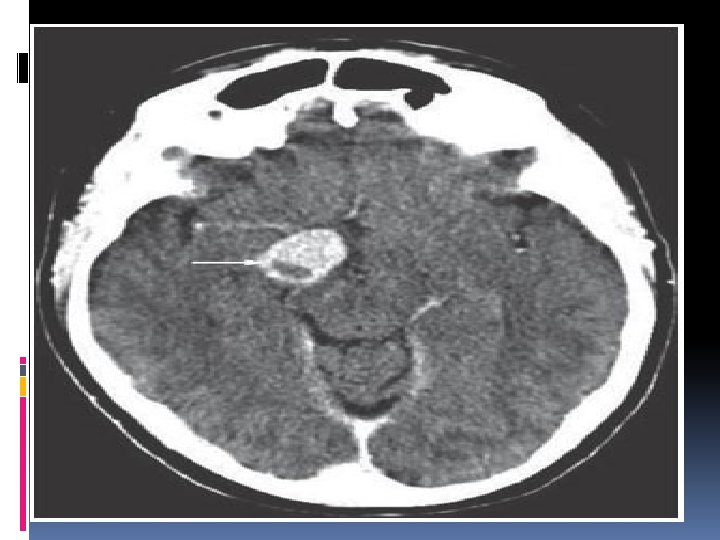

Neuroimaging studies C. T SCAN of sella with thin slices(1. 5 -2 mm)plus contrast , to exclude ac. Haemorrhage. MRI of sellar & parasellar(<2. 5 mm slices) Cerebral angiography or MRI angio to exclude aneurysms.

Pituitary apoplexy Acute haemmorrhagic necrosis of a pituitary adenoma&adjacent pituitary tiss. Predisposing factors: pregnency, endocrinologic manipulations(estrogen adminstration, bromocriptine medication), H. injury, chronic cough&sneezing, anticoagulant drugs, cerebral angio. , radiotherapy

Symptoms &signs Headache, nausea & vomiting, diplopia&visual impairment, compression of cranial n. s in one or both cavernous sinuses, ophthalmoplegia, meningeal irritation, photophobia Diagnosis(MRA, ANGIO, CT, CLINICAL) Treatment : surgery